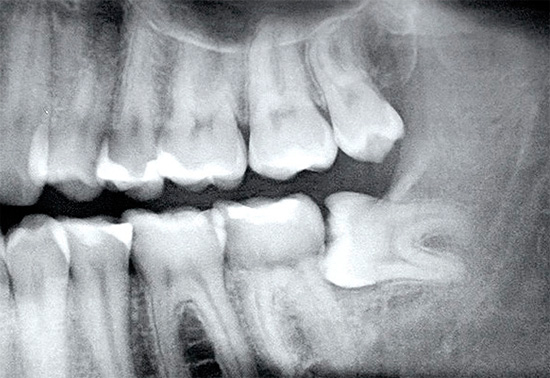

Como o dente do siso costuma ter uma localização não padrão e um grande número de raízes, um raio-X é sempre realizado antes da remoção complexa. Muitos cirurgiões-dentistas não realizam a remoção de um dente do siso sem uma imagem, exceto nas situações mais emergenciais ou quando não é possível fazê-lo imediatamente por várias razões.

A natureza da complexidade da intervenção é determinada pelo cirurgião-dentista em uma instituição especializada e, como observado acima, a remoção nunca começa sem um raio-X. A complexidade de sua remoção depende da natureza da localização do dente no orifício. Se o dente estiver localizado completamente no osso e quase estiver ao longo da mandíbula, a operação poderá demorar muito tempo, à medida que as gengivas forem excisadas, o osso será cortado com a separação da coroa e das raízes dos dentes, seguido de uma extração em fases do orifício ósseo.